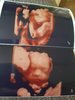

Dawno mnie niebylo ale czytam was codziennie dzis bylam.na 3 d usg z dziecmi 100% dziewczynka wazy 540 gram 31 cm zaslaniala raczka caly czas twarzyczke ale dalo sie pare zdjec zrobic

54,9 KB · Wyświetleń: 362